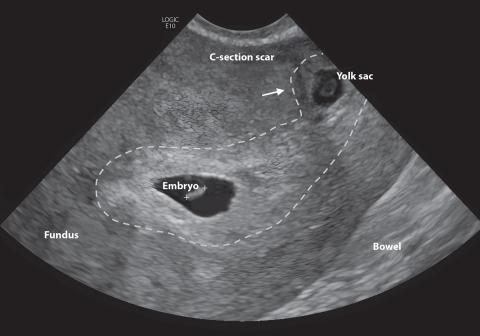

History

A pregnant woman in her mid-30s presented to the emergency room with acute onset of back and pelvic pain and moderate spotting. The patient was gravida 4, para 2 (G4P2) and had had two prior cesarean sections... Read More